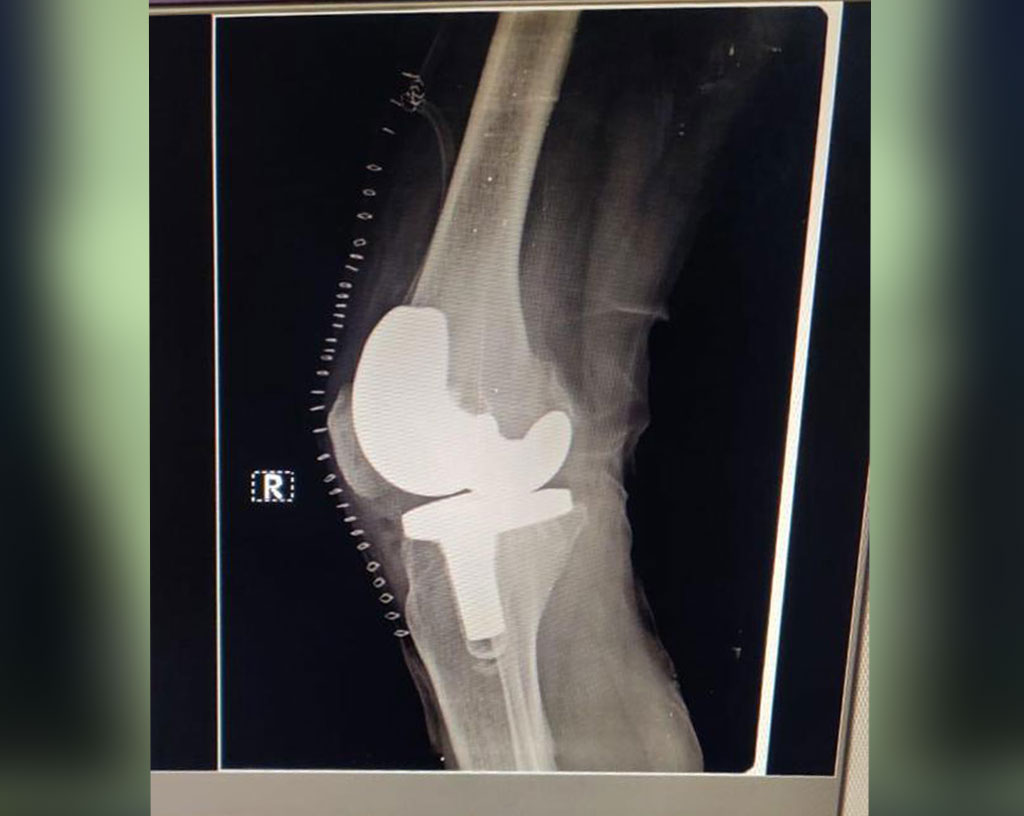

Total Knee Replacement

Name: RL Bansal

Date of Operation: 16 Feb 2021

Age: 72 Years

After Surgery